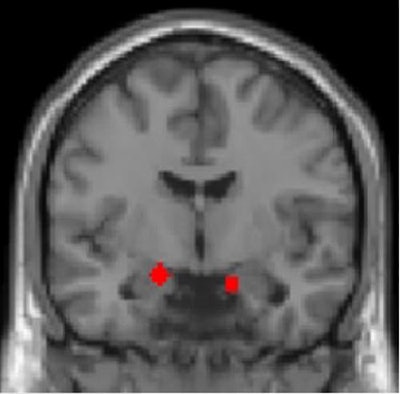

Functional MRI of combat veterans showed that the amygdala -- defined functionally in red -- is a particularly important area of the brain for predicting severity of PTSD symptoms. Image courtesy of Ilan Harpaz-Rotem, PhD; Daniela Schiller, PhD; and Nature Neuroscience.

Functional MRI of combat veterans showed that the amygdala -- defined functionally in red -- is a particularly important area of the brain for predicting severity of PTSD symptoms. Image courtesy of Ilan Harpaz-Rotem, PhD; Daniela Schiller, PhD; and Nature Neuroscience."What these results tell us is that PTSD symptom severity is reflected in how combat veterans respond to negative surprises in the environment -- when predicted outcomes are not as expected -- and the way in which the brain is attuned to these stimuli is different," said Schiller in a statement from the NIH. "This gives us a more fine-grained understanding of how learning processes may go awry in the aftermath of combat trauma and provides more specific targets for treatment."